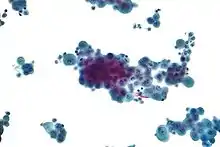

- If cancer is suspected, the pleural fluid is sent for cytology. If cytology is negative, and cancer is still suspected, either a thoracoscopy, or needle biopsy[5] of the pleura may be performed.

Micrograph of a pleural fluid cytopathology specimen showing malignant mesothelioma, one cause of a pleural effusion.

- Cytopathology to identify cancer cells, but may also identify some infective organisms